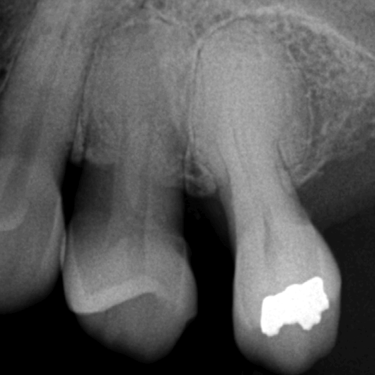

Granuloma Periapical

Un granuloma periapical es una pequeña masa de tejido inflamatorio en la punta de la raíz del diente, generalmente como respuesta a una infección crónica.

Los pacientes pueden no sentir dolor, pero el área puede estar sensible al tacto.

El tratamiento de conducto es necesario para eliminar la fuente de la infección y permitir la curación del tejido.